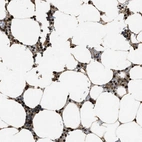

Immunohistochemical staining of human bone marrow shows strong nuclear positivity in hematopoietic cells.